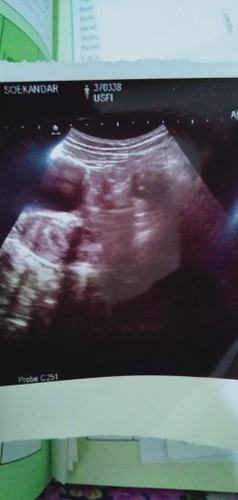

hamil 4 Minggu 3hari

Bunda.. aq Senin kemarin USG.. hasilnya gini.. Dedeknya kecil bgt.. apa uk segitu normal.. maklum.. hamil kedua .. tp yg pertama baru tau hamil pas udh keguguran.. jd kurang pengalaman.. makasih bund

Kalo kta dokter semua ckup gpp bun